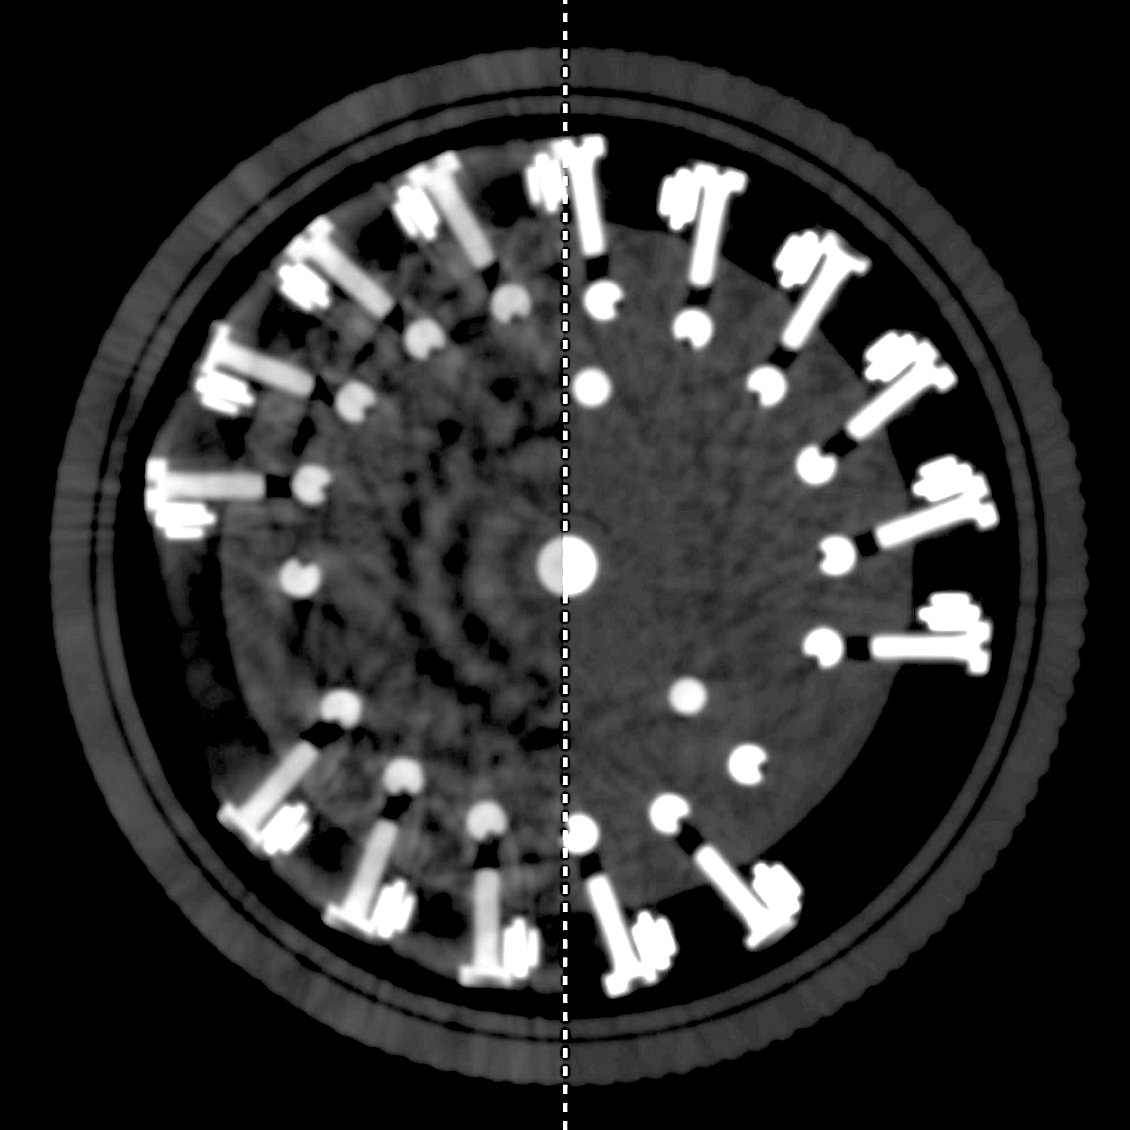

A new review article authored by members of the Contrast Team (Lara Mazy and @GreetKerckhofs) on combined in situ testing and X-ray microfocus computed tomography for biological application.